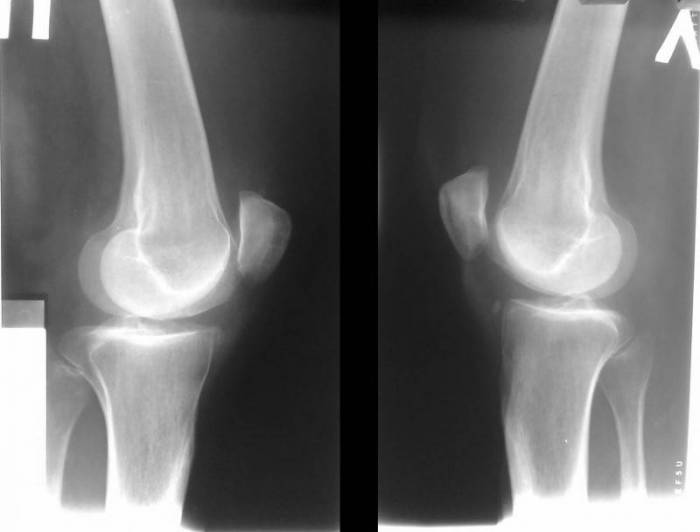

Суставная мышь может возникнуть при любом из таких заболеваний суставов, как:

- Травматическое повреждение сустава, гемартроз (скопление крови в полости сустава);

- Деформирующий артроз;

- Хондроматоз (болезнь Кенига).

Так, воспаление сустава приводит к отторжению частиц капсулы, которые приобретают в полости сустава смешанный костно-хрящевой характер. Кровь, излившаяся в полость сустава при травме, приводит к формированию свободно перемежающихся и ни с чем не связанных сгустков фибрина, прорастающих плотной соединительной тканью.

Внутрисуставные мыши чаще формируются в коленном и локтевом суставах. В большинстве случаев они единичные, но бывают случаи, когда обнаруживают и более пяти в одном суставе. Форма и размеры также очень различны и часто зависят от случайных факторов.

Болезнь Кенига. В коленном суставе происходит отслоение участка хрящевой поверхности. Артроскопия.

Та самая суставная мышь на срезе томограммы.

Самая частая локализация суставной мыши — коленный и локтевой сустав. По размеру: от небольших, 1-2 мм, до довольно значительных (коленный сустав), 1-1,5 см. Чаще всего единичные, но бывают случаи, когда выявляются более пяти фрагментов.